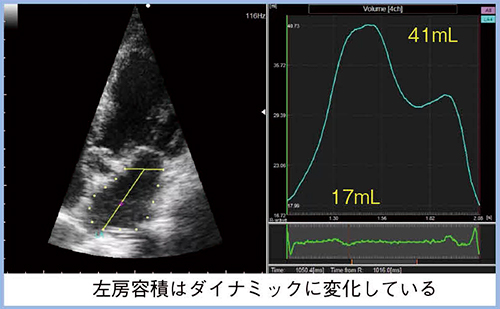

2.左房容積の時相変化の計測

前述のとおり,LAVIは有用な左房拡大指標であるが,一方で,特に左房圧推定においてはその限界が指摘されている5)。利尿剤の投与などによって左房圧が低下しても,LAVIは容易に改善しないことから,より鋭敏な左房拡大指標の探究が進んでいる。その一つが最小左房容積(LAVmin)であり,最大左房容積(LAVmax:LAVI)よりも心房細動の発症予測に優れた指標であることが報告された6)。

日立の超音波診断装置では,“2D Tissue Tracking”(2DTT)により左房容積の時相変化をダイナミックにトラッキング可能である(図2)。左房は,心電図のQRS波のR波の始点でLAVmin,T波の終わりにLAVmax,U波の前にpre-Aの時相(左房収縮直前)の容積(LAVpre-A)へと変化する。そして,LAVmin,LAVmax,LAVpre-Aの境界時相の容積は,それぞれ左房のreservoir(貯留)機能,conduit(導管)機能,booster pump(後押し)機能を表している(図3)。また,LAVmaxとLAVminから求められるLA emptying fraction(LAEF)は,総合的左房リザーバ機能指標とされており(基準値:LAEF<50%),左房容積とLAEFの組み合わせは,心房細動の出現予測に有用であることが報告されている7)。

図2 2DTTによる左房容積の時相変化の計測